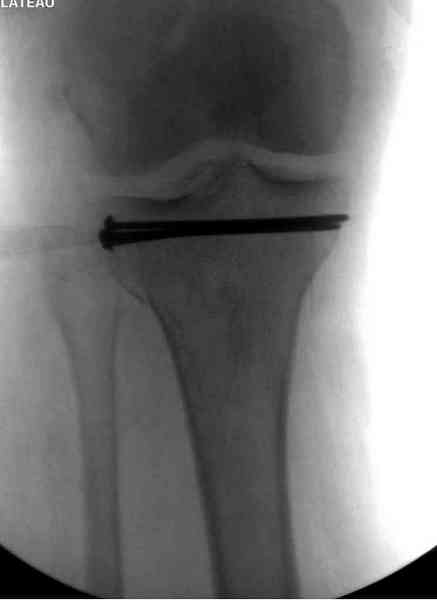

Снимки до и после закрытой репозиции

На представленном после операционном снимке нет репозиции, на что указывает низкое положение тибиального плато и перекрытие кортикальных пластинок в метафизарной части - указано стрелкой. Обычно чрескожную фиксацию я применяю

Пациентки прооперирована, результат чего на снимках. Выполнена открытая репозиция костей правой голени, синтез малоберцевой пластиной, б/берцевой винтами, имеющиеся фиксаторы не подходили, было принято решение репонировать отломки, синтез винтами, гипсовая повязка.

Мыщелок левой б/б кости репонирован закрыто, на контрольной рентгенограмме репозиция удовлетворительная, фиксировано спицами. гипсовая повязка.

Репозиция внутрисуставных переломов неудовлетворительная и не адекватна.

сценарий и для перелома наружного мыщелка б.б.- передний фрагмент стоит на месте, а задний не репонирован - в таком положении оставлять фрагменты нельзя, суставная поверхность должна быть реконструирована.

В лечении переломов пилона восстановление длины малоберцовой является индикатором и ориентиром для успешного лечения. Первый этап восстановления по длине не удался, малоберцовая остается короткой, и репозиция суставной поверхности осталась неудовлетворительной. Длина передней колонны не восстановлена, а в дистальном фрагменте имеется флексия. Оставлена без внимания потеря кости в метафизе. Шурупы 4.5 мм будут выступать после спадения отека, и возможно будут причиной мягкотканого осложнения в гипсе.